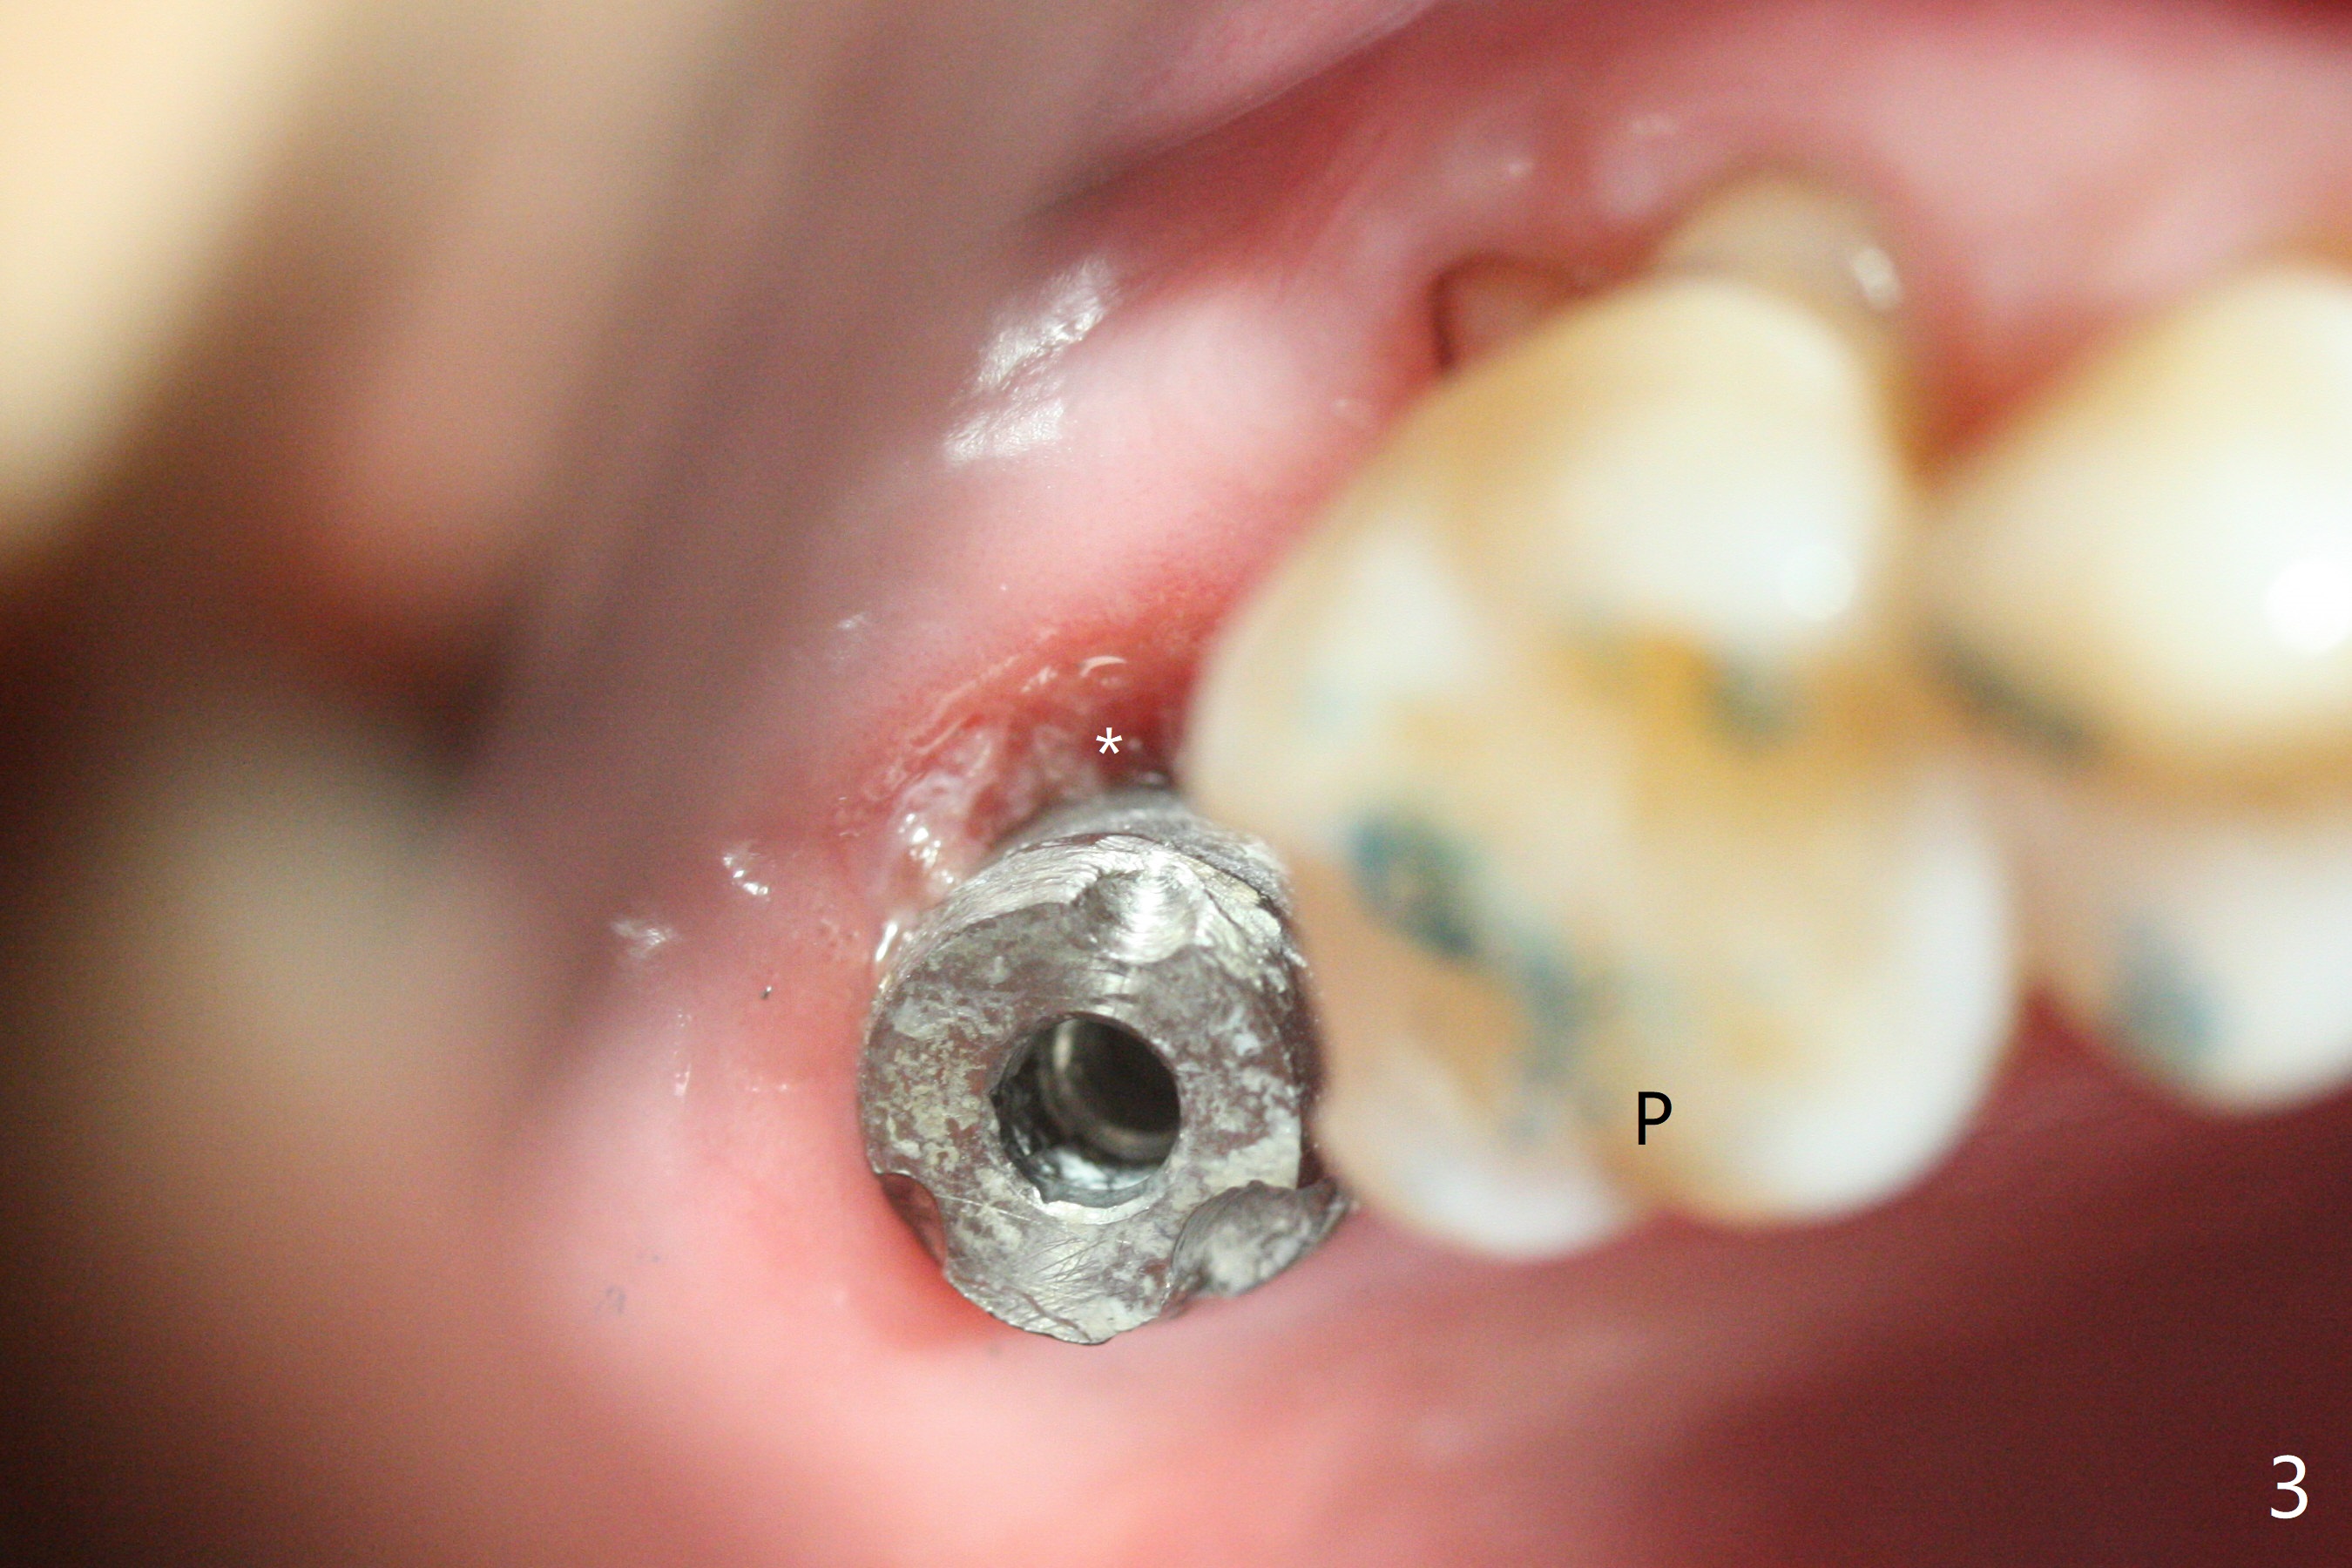

50岁男,二型糖尿病,对常用糖尿病药物无效,使用胰岛素也必须提高剂量,总之控制不好。总共种植四个,两个延期没问题,但是两个即刻均失败,似乎容易发炎,包括右上7(图一:* (螺纹暴露)),颊侧牙龈退缩(图二),牙冠取出后显示植体和基台偏腭侧(图三:P),其实植体没有整合,不费劲旋出植体,清除肉芽组织后,植入粘性骨粉(图四:*),覆盖PRF膜,GEM Cap,应用牙周胶水固定,然后间隙维持器,牙周敷料固位。右上7和左上7植牙取出后4个月和一年5个月骨质高度很低(图五)。右上7大约1.8毫米(图六)。准备植入5x7毫米植体(图七)。使用1毫米stopper钻头,然后Magic Lifter和PRF。术前口服Z Pack,术后Medrol Dose Pack。